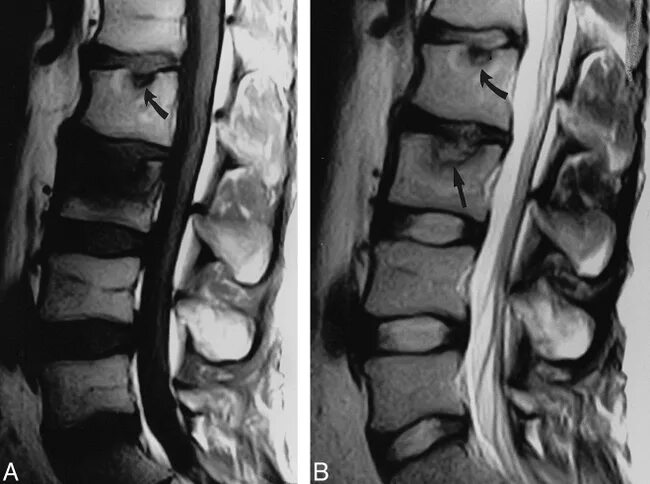

Протрузии шморля